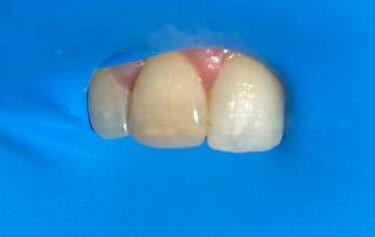

Then, the medicament was changed to calcium hydroxide, which was changed every 12-15 weeks. After 6 months, a periapical surgical procedure was performed in order to remove the broken instrument from the apical area of tooth 12 while tooth 11’s root canal was filled with GP cones and Ah-26 cement. Upon patient’s request, internal whitening was also done for his tooth 11, followed by a composite filling 1 week later.

After the first session of internal whitening

After the second session of internal whitening